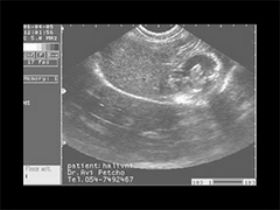

עוד עובר מקסים בן 6 שבועות